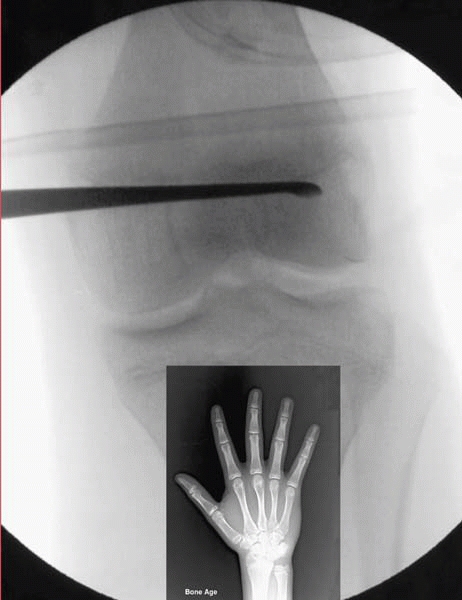

velocity of the pubertal growth spurt (Fig. 1-2).

The triradiate cartilage closure tells you that the adolescent is

two-thirds of the way through the most rapid phase of growth. At

menarche in girls and the first shaving episode in boys, the adolescent

will generally be at Risser I. Tanner staging is much more accurate,

but most orthopaedists do not feel that they are comfortable making

this a routine part of the musculoskeletal exam. Dr. Kasser recommends

when timing any operation for which the stage of growth remaining is

important for a good result, the best way to stay out of trouble is to

ignore chronologic age and focus on bone age. Very little lower limb

growth occurs after a bone age of 13 in a girl and 15 in a boy. Also,

bone age will often accelerate during puberty. Stay out of trouble by

shortening the followup for an epiphysiodesis visit from 6 months to 4

months and always order a bone age during this period.

▪ FIGURE 1-2 A.

The olecranon ossification center can act as a helpful guide early in puberty, because it signals the start of the most rapid period of growth. Stage 1 occurs long before the closure of the triradiate cartilage, or menarche. The graph depicts the steep part of growth—a time period you miss completely if you are waiting for Risser I B. Dimeglio’s summary diagram of growth, presented combined with Tanner findings in boys. By the time you see axillary or facial hair on exam, the fastest period of growth is over. C. Dimeglio’s summary diagram of growth, presented combined with Tanner findings in girls. (Reprinted with permission from Morrissy RT, Weinstein SL, eds. Pediatric Orthopaedics, 5th ed. Philadelphia: Lippincott Williams & Wilkins, 2001.) |

Olecranon ossification and bone age are much more reliable than Risser sign in assessing the most rapid period of growth.